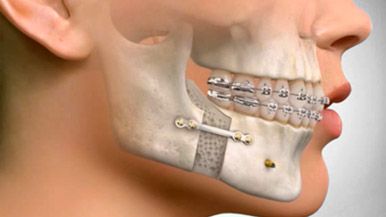

Orthognathic Surgery

Perhaps your dental issues stem from a joint problem called TMJ and you do not want to crown your teeth in order to restore the bite. Our Maxillofacial Surgeon is qualified to perform Orthognathic Surgery to help correct these TMJ issues. Orthognathic Surgery is usually done after or before an Orthodontic treatment. Contact a Dental Coordinator for questions regarding your case.